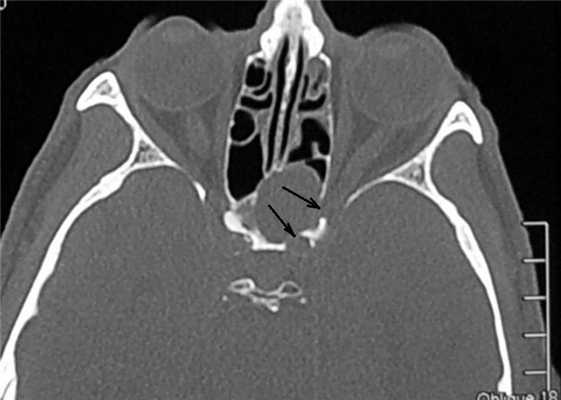

В рамках предоперационной подготовки для представления об объеме костной деструкции выполнена КТ околоносовых пазух. Обнаружена эрозия костного канала зрительного нерва слева, костного канала левой внутренней сонной артерии (рис. 1). Рисунок 1. Компьютерная томограмма ОНП (аксиальная проекция) больного Е. Затемнение обеих клиновидных пазух, дефекты костного канала зрительного нерва слева, костного канала левой внутренней сонной артерии (указано стрелками). Принято решение о необходимости эндоскопической сфеноидотомии с ревизией клиновидной пазухи и, при необходимости, удалении новообразования с последующим его гистологическим исследованием. Предоперационный диагноз: новообразование клиновидной пазухи. Паралитическое косоглазие слева.